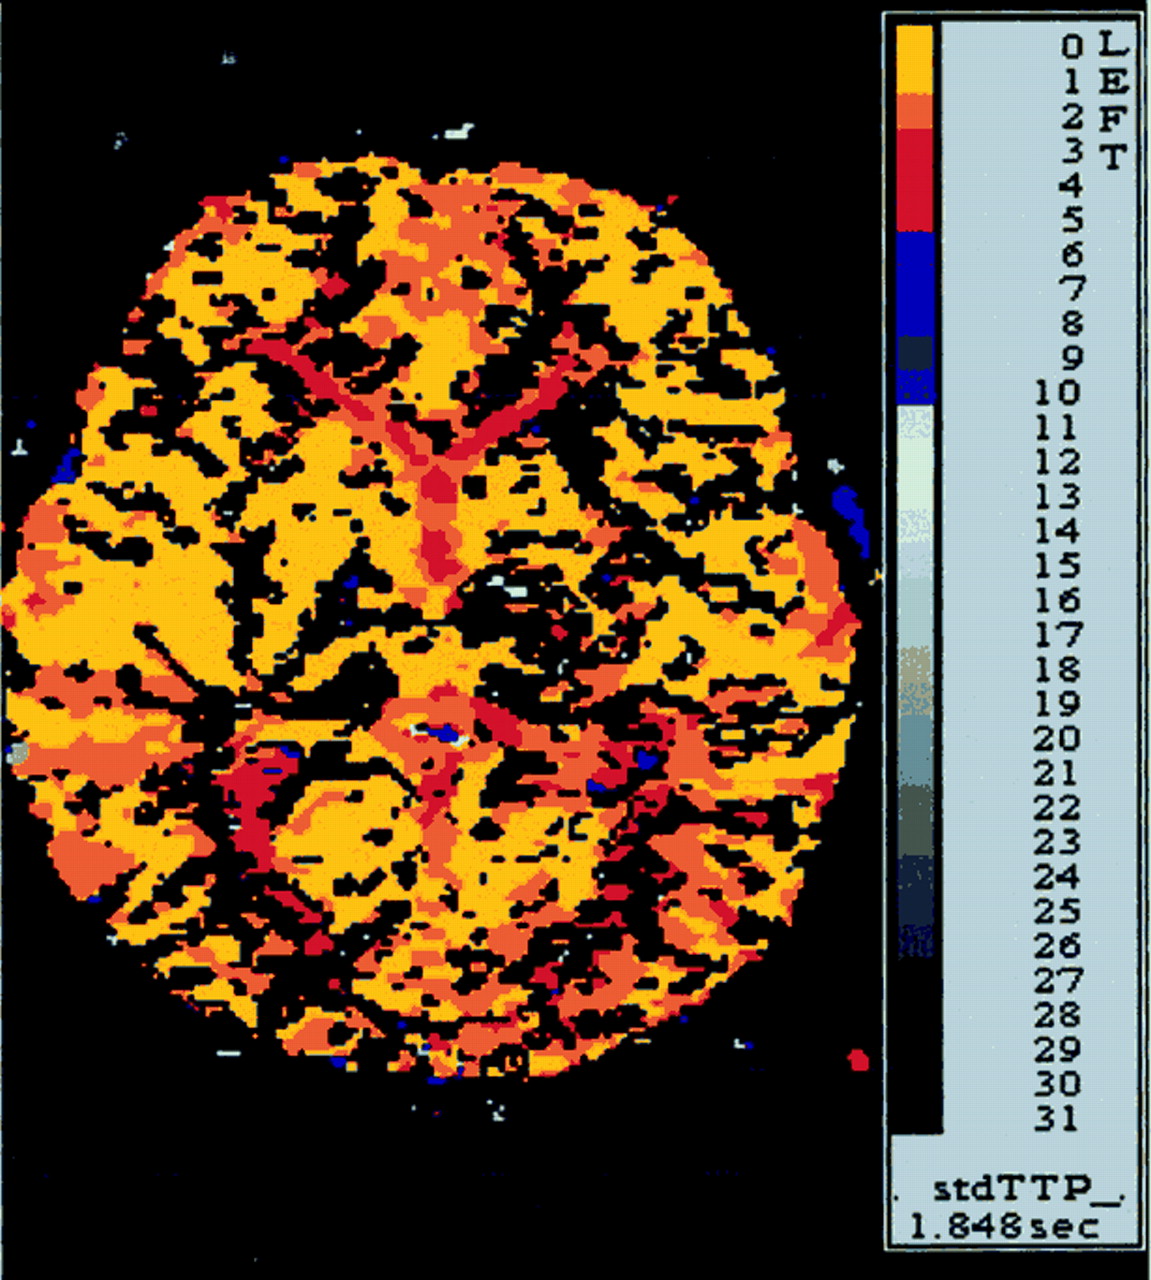

病人气管切开后的第二天点燃,能够将第二天左胳膊和腿。一周后,这个孩子被动态。点燃了两周后,病人没有残疾在日常生活活动或休闲活动。她经历了一个最小的干扰,同时保持一个较高的位置左胳膊。考试成绩的运动强度(手测功器)和finger-hand协调(手指敲击,将挂钩孔)是在正常范围内。神经心理学评估显示没有语言障碍的迹象,认知或行为。MRI显示一个小纹状体梗死保留内囊(图1 b)。时间进程和振幅的电位诱发外展digiti最小的经颅磁刺激肌肉的皮质是在正常范围内,表示对称完整锥体束功能(延时的左臂,13.8毫秒;延迟的右臂,11.2毫秒)。灌注加权核磁共振没能证明正确的MCA血流动力学妥协领土(图3)。